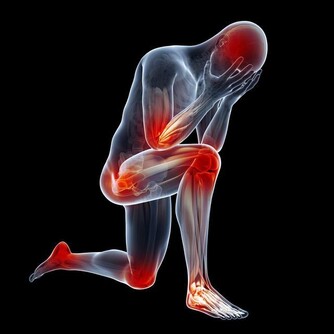

除此之外,起床後眼皮浮腫、腰酸乏力可能是腎病初期的表現,小便紅、小便時泡沫較多且持續時間長,四肢、臉上、身上的皮膚出現較多的紅點或紅斑,四肢關節酸痛等都應引起警覺。

尿毒症正在走向年輕化,所以年輕的朋友們,不要再以自己年輕做為健康資本,保護腎臟,除了定期檢查外,應不憋尿、多喝水,飲食清淡、減少食鹽攝入,避免濫用藥物、長期大量服用止痛劑,不吸煙、少喝酒。